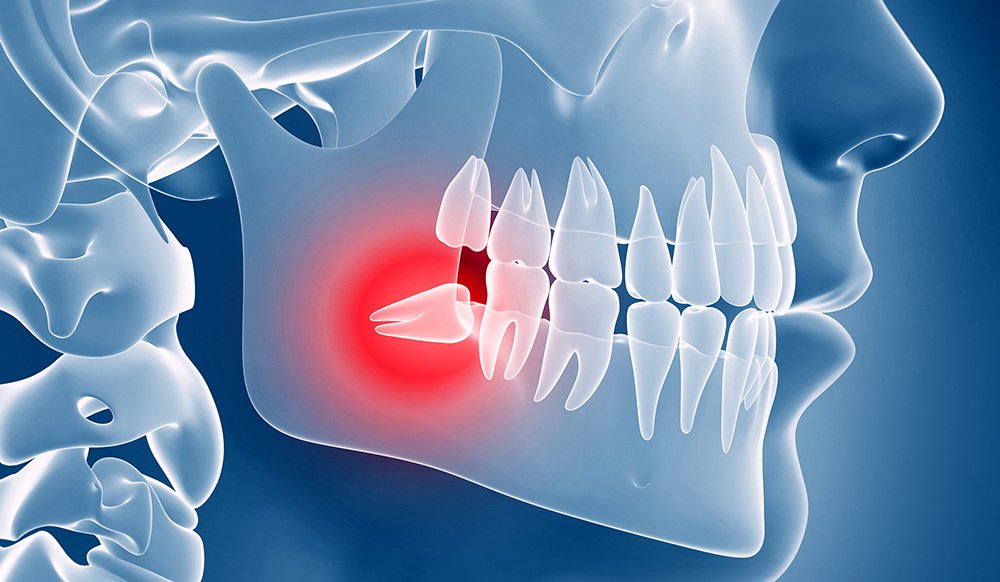

Chirurgia Endorale: Soluzioni Efficaci per lesioni apicali

La Chirurgia Endodontica è l’intervento di elezione quando il normale trattamento canalare non è sufficiente. Può essere necessaria per lesioni apicali, perni cementati nella radice o per posticipare l’estrazione e l’inserimento dell’impianto. Con una percentuale di successo dell’80%, l’intervento viene eseguito ambulatorialmente in anestesia locale, garantendo risultati durevoli.